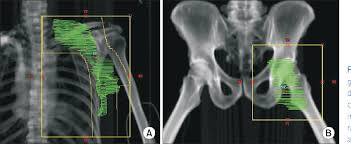

Groin Area Skin Cancer Groin : Vulvar Cancer Causes Symptoms And Treatments - A surgical procedure called a sentinel lymph node biopsy (slnb) removes the first lymph node in a chain or group of lymph nodes that a particular cancer is most likely to spread to.

After surgery, i had 4 treatments of a combination of carboplatin and taxol, followed by 25 radiation treatments to the area. The cancer has spread to distant parts of the body (any t, any n, m1). In rare cases, hip pain is caused by cancer of the bone or cartilage in the hip joint. The cancer has spread to 1 or more of the pelvic lymph nodes (any t, n3, any m). You may also massage the area for a few minutes.